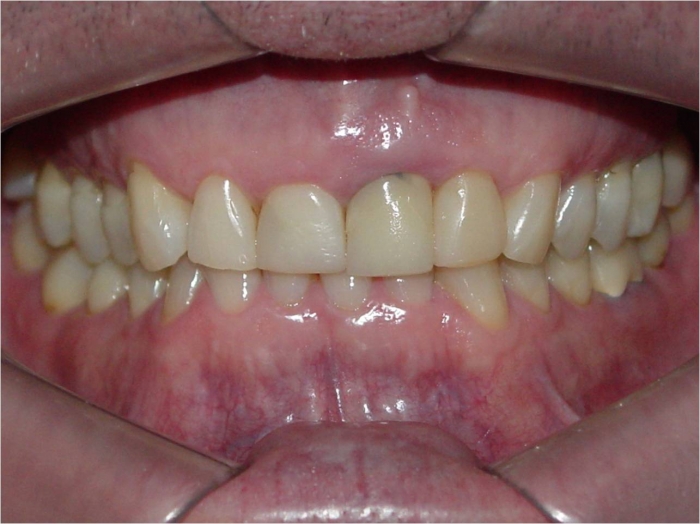

Sorriso inicial